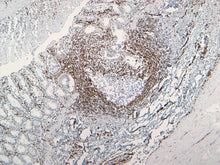

Description: This monoclonal antibody recognizes vimentin, which is the main intermediate filament protein present in cells of mesenchymal origin. This antibody does not show cross-reactivity with other closely related intermediate filament proteins such as Desmin and GFAP.

This marker has been shown to be helpful in labeling mesenchymal-derived tumors such as lymphomas, sarcomas, and melanomas. The expression of vimentin has also been suggested to be an indicator of tumor progression and potential for metastasis as a marker for epithelial-mesenchymal transition.

Positive Control: Sarcomas and Melanomas